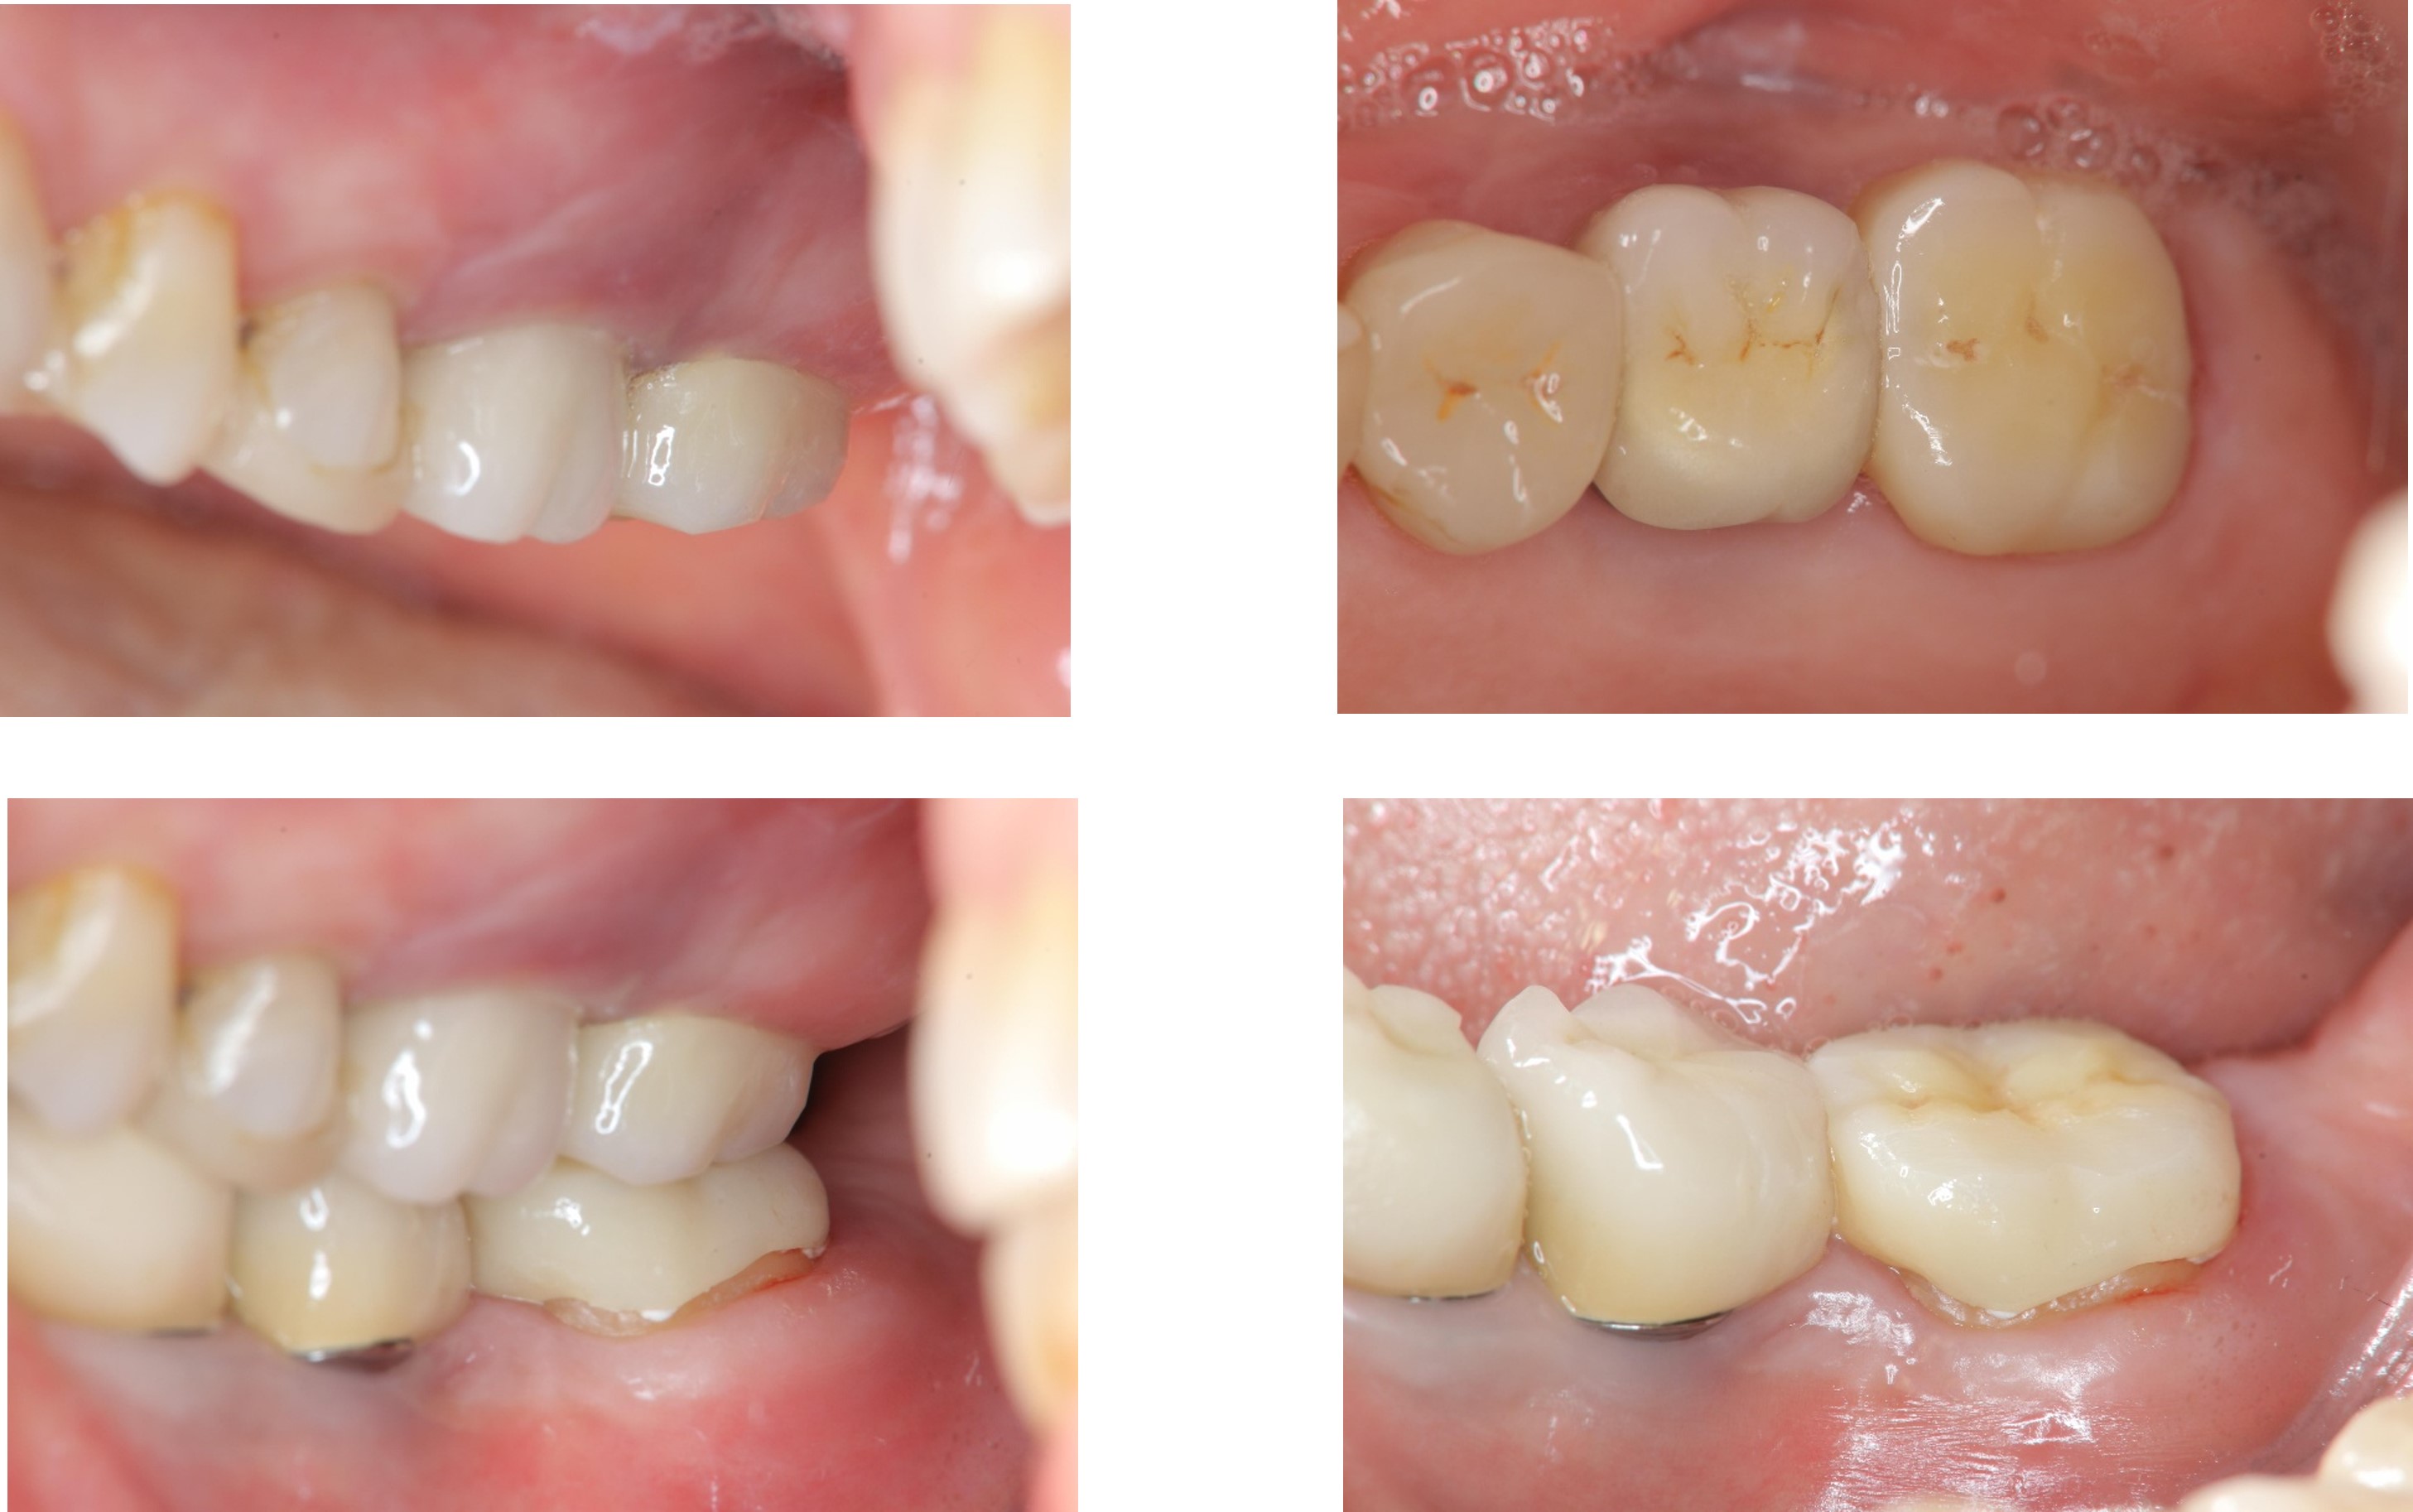

全鋯冠

治療後,牙周咬合良好

治療後,密合度良好

術前、術後比較